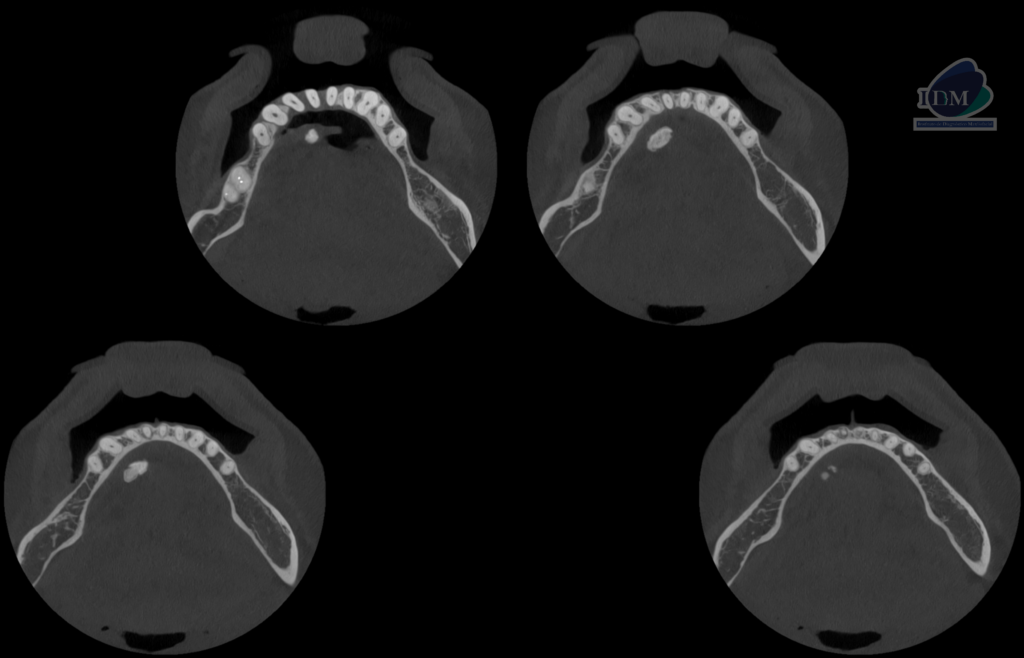

A la evaluación de la tomografía volumétrica (CBCT) en los cortes axiales (Figura 2) y transaxiales (Figura 3), se aprecia imagen hiperdensa de densidad cálcica localizada en lingual del cuerpo mandibular derecho a nivel de tercio apical de piezas 43 y 44, de limites definidos, forma irregular.

CORTES TRANSAXIALES